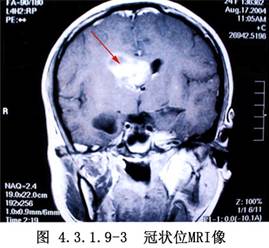

側腦室內腫瘤的發生率較低,據國內外文獻報道約佔顱內腫瘤總數的0.75%~2.8%。在側腦室前部和體部者,多爲室管膜瘤,在三角部、顳角和枕角區者,多爲乳頭狀瘤或腦膜瘤。側腦室周圍、丘腦和腦室室管膜下生長的膠質瘤,也可長入腦室內。其他如上皮樣囊腫或皮樣囊腫等也偶可見到。側腦室內腦膜瘤約佔顱內腦膜瘤的2.5%~6.3%,以女性較多,年齡多在30歲左右,且好發於左側側腦室。室管膜瘤則以嬰幼兒和學齡前兒童多見(圖4.3.1.9-1~4.3.1.9-6)。

頸動脈造影顯示脈絡膜前動脈增粗,椎動脈造影顯示脈絡膜後動脈增粗、走行異常和腫瘤染色等,都是確診側腦室腫瘤的有力依據。自CT、MRI問世以來,確診已較簡易、安全。由於手術經驗的積累,療效亦不斷提高,大多能全切治癒。